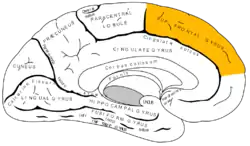

Medial surface of left cerebral hemisphere. | |

The superior frontal gyrus is situated above the superior frontal sulcus and is continued on to the medial surface of the hemisphere, the medial frontal gyrus. The medial and superior frontal gyri are two of the frontal gyri of the frontal lobe. The portion on the lateral surface of the hemisphere is usually more or less completely subdivided into an upper and a lower part by an antero-posterior sulcus, the paramedial sulcus, which, however, is frequently interrupted by bridging gyri.